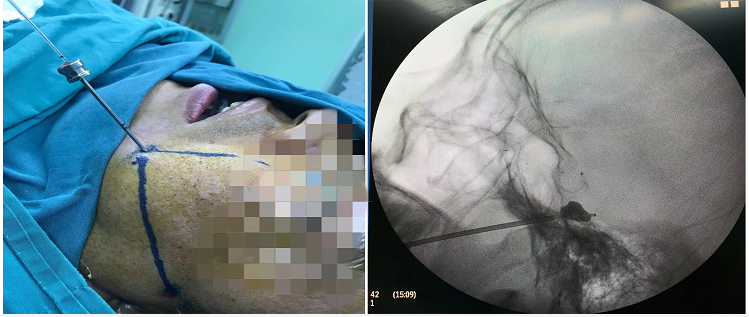

刘大爷为典型的三叉神经第二、三支疼痛(下牙槽、上牙槽和鼻孔),偶可波及额头,经过相关检查后确诊为原发性三叉神经痛,并建议可以选择做“三叉神经微血管减压术”(开颅手术)和“经皮穿刺三叉神经半月节微球囊压迫术”(微创手术),但患者及家属担心开颅手术创伤大、风险高及后遗症重,对开颅手术一直存在抵触。“经皮穿刺三叉神经半月节微球囊压迫手术”属于微创手术,只需要在脸上打个针眼,通过特殊的手术器械压迫三叉神经半月节而达到治疗目的,手术时间短、创伤小、恢复快,家属和病人欣然同意行微创手术。很快就给刘大爷安排了微创手术,手术时间约30分钟完成,术后刘大爷面部疼痛立即消失,术后第2天便出院,现随访半年疼痛没有复发,被三叉神经痛困扰的刘大爷如获新生,对生活又充满了希望。

三叉神经痛一般首选药物、射频消融术等治疗方式,这些方法简单,却容易复发。三叉神经微血管减压术是目前治疗三叉神经痛最常用手术方法,科室已拥有多年的手术经验,但微血管减压术是开颅手术,有一定限制且部分病人不愿接受。经皮穿刺微球囊压迫半月节术只需短暂的全身麻醉,在C臂透视下精准穿刺,利用球囊压迫三叉神经半月节,手术只需在脸上穿刺一针即可完成,术后疼痛即刻缓解率可达95%以上,该手术效果确切、并发症少、恢复快、费用低、住院时间短,特别适合用于高龄、不耐受或不接受开颅手术、合并基础疾病、身体条件较差等情况的患者。(文/图 神经外科 马元施)